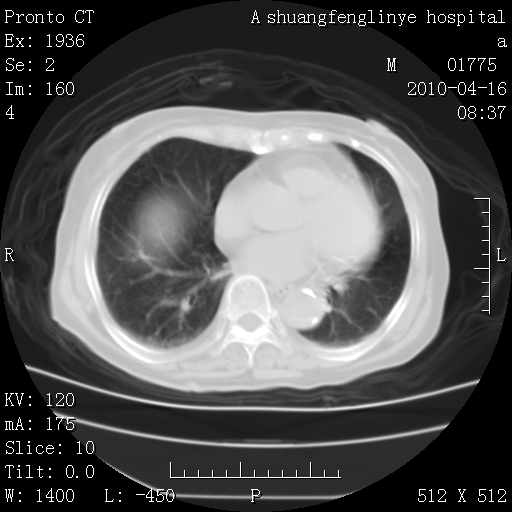

考虑左肺上叶增殖灶、纤维灶。

支持结核

慢支肺气肿,左上陈旧性结核,主动脉冠脉钙化

1)左肺上叶结核(纤维、增殖病灶)。2)冠状动脉及主动脉钙化。

1)左肺上叶结核(纤维、增殖病灶)。2)冠状动脉及主动脉钙化。肺动脉高压